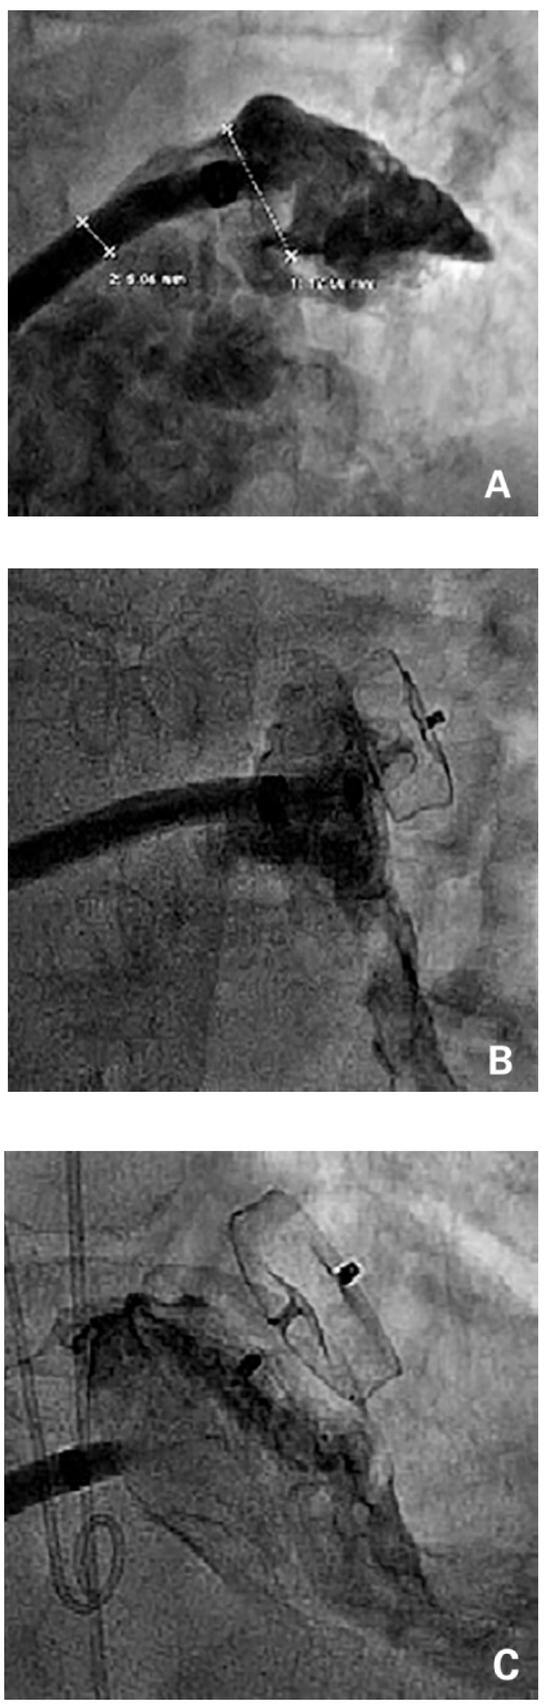

Vasospastic angina is a clinical disorder primarily attributable to coronary artery spasm and typically characterised by a history of rest angina that promptly responds to short-acting nitrates. In this case report, we describe a 72-year-old man affected by vasospastic angina, who presented with asymptomatic transmural ischaemia during a routine exercise stress test and paradoxical subocclusive coronary spasm, superimposed on a non-significant coronary stenosis, following intracoronary nitroglycerin injection during coronary angiography. Other cases of paradoxical vasospastic response to nitrates during coronary angiography have been already described in literature. However, in these previously described cases, coronary spasm occurred in a portion of the vessel close to the catheter tip or following sublingual nitroglycerin administration, thus making it difficult to clearly assess the possible causative relation between nitrate administration and coronary spasm. This represents, to the best of our knowledge, the first described case of paradoxical coronary spasm occurring a few seconds after direct intracoronary nitroglycerin injection and in a portion of the vessel far enough from the catheter tip to exclude late-onset catheter-induced spasm in the absence of any catheter-tip drop-in or deep intubation. A paradoxical vasospastic response to nitrates in vasospastic angina patients represents a rare but very challenging condition. Thus, the best therapeutic approach in this subgroup of patients remains unclear. In our patient, because of the transmural ischaemia documented during the exercise stress test, a percutaneous coronary intervention (PCI) was performed and the clinical evolution was favourable. Therefore, we believe that PCI might represent an effective therapeutic option in vasospastic angina patients with a paradoxical response to nitrates and focal epicardial coronary spasm. Full article

Figure 1